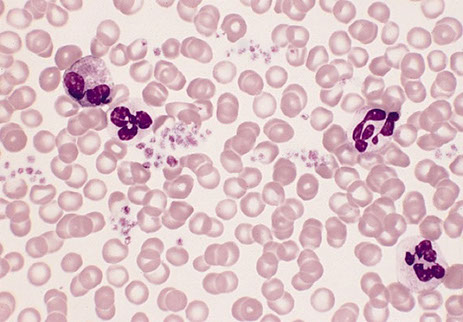

PB findings

Thrombocytosis 1000 X 10^9/L.; large platelet aggregates

Platelet anisocytosis; bizarre forms (agranular, pseudopods)

- Occasional megakaryocyte fragments

- Target cells, acanthocytes, and Howell-Jolly bodies if splenic infarction.

ET - peripheral smear

Essential Thrombocythemia

Megs look like staghorn nuclei in the biopsy, and like a bunch of grapes in the aspirate [2]